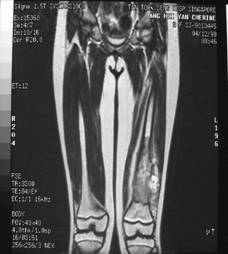

Pre Op

X-ray (Left femur)

osteolytic lesion

(?) osteosarcoma